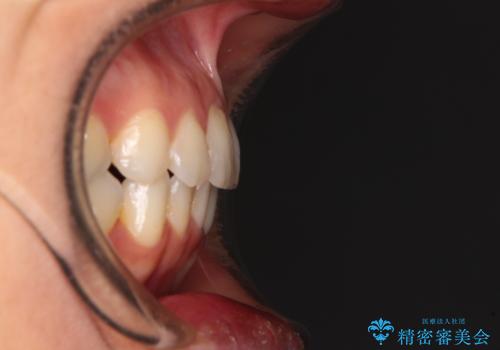

前歯の叢生をいつの間にか改善 インビザラインによる矯正治療

- 前歯のデコボコを気にして来院された患者様です。

IPR(歯と歯の間を削る)によってデコボコが解消するように設計し、インビザラインにより治療を行うこととしました。

下顎善の叢生をもう少し改善したかったのですが、患者様は十分に整ったとのことで治療を終えることになりました。